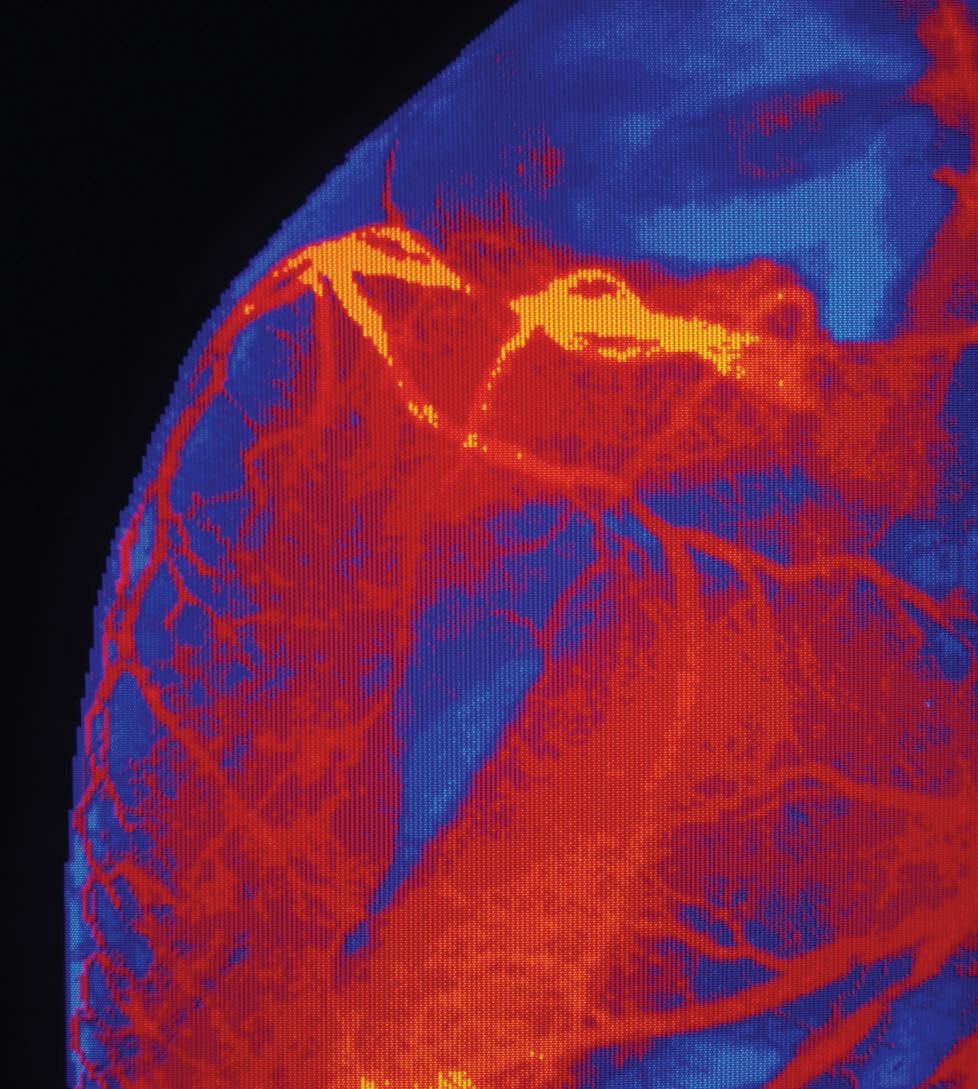

Why 25 years of patient-centered innovation really matters

One mainstay endovascular aneurysm repair (EVAR) device is celebrating not just a quarter century of being commercially available, but the innovation it has inspired along the way. Michel Makaroun, MD, and Willy Davison, PhD, discuss the evolution and innovation of the GORE® EXCLUDER® device family over time.

Twenty-five years of patient impact and durability is worth celebrating in the life of any medical device. And when a device reaches this milestone, it is celebrating more than just 25 years in the treatment landscape. It is a legacy of making a difference for physicians and their patients.

The GORE ® EXCLUDER ® AAA Endoprosthesis for abdominal aortic aneurysm (AAA) is commemorating 25 years of commercial availability since earning its CE mark in September 1997. It has been used to treat more than 440,000 patients worldwide* and has become the most-studied EVAR device according to company-sponsored trials and registries shown on ClinicalTrials.gov for currently available stent grafts.

“The EXCLUDER® AAA Endoprosthesis has been on the market helping patients for well over two decades: A truly remarkable accomplishment and the longest stretch in the industry,” said Makaroun, chief of the Division of Vascular Surgery at the University of Pittsburgh Medical Center and an investigator in each EXCLUDER® device clinical study.

“The close collaboration between medical community and manufacturer has allowed for numerous innovations and improvements along the way, providing for more accurate deployment and better outcomes.”

“As EVAR became more prevalent and additional patient needs were uncovered, it was important that W. L. Gore & Associates—the global materials science company behind the device—continue exploring and improving EVAR solutions,” said Davison, Abdominal Aortic Global Business leader at Gore.

“We recognized the broader potential of the device but knew that there was still a need to keep improving, keep innovating, to help address even more patients’ unique needs and anatomies.”

Over the next two decades, Gore developed and studied additional solutions within its EVAR portfolio, receiving approvals for larger trunk and contralateral limb diameters, an iliac branch device, and a next generation of the EXCLUDER® device that is conformable and offers optional angulation control—allowing physicians more treatment options to consider for their patient’s anatomy.

Pre-implant

Davison said that at Gore, collaboration with the medical community is key to developing solutions that continue to advance patient care. “We are immensely grateful to the physicians who have put their trust in our devices to help their patients maintain their quality of life and those who have partnered with us as we continue exploring future solutions for AAA patients,” he said.

For more information on the GORE® EXCLUDER® AAA Endoprosthesis and the GORE® EXCLUDER® device family, scan the above QR code.

2004

EXCLUDER® device design features a nitinol stent, sutureless stent-to-graft attachment and proprietary ePTFE film layers

Four-year follow-up showing aortoiliac aneurysms treated with bilateral iliac branch devices